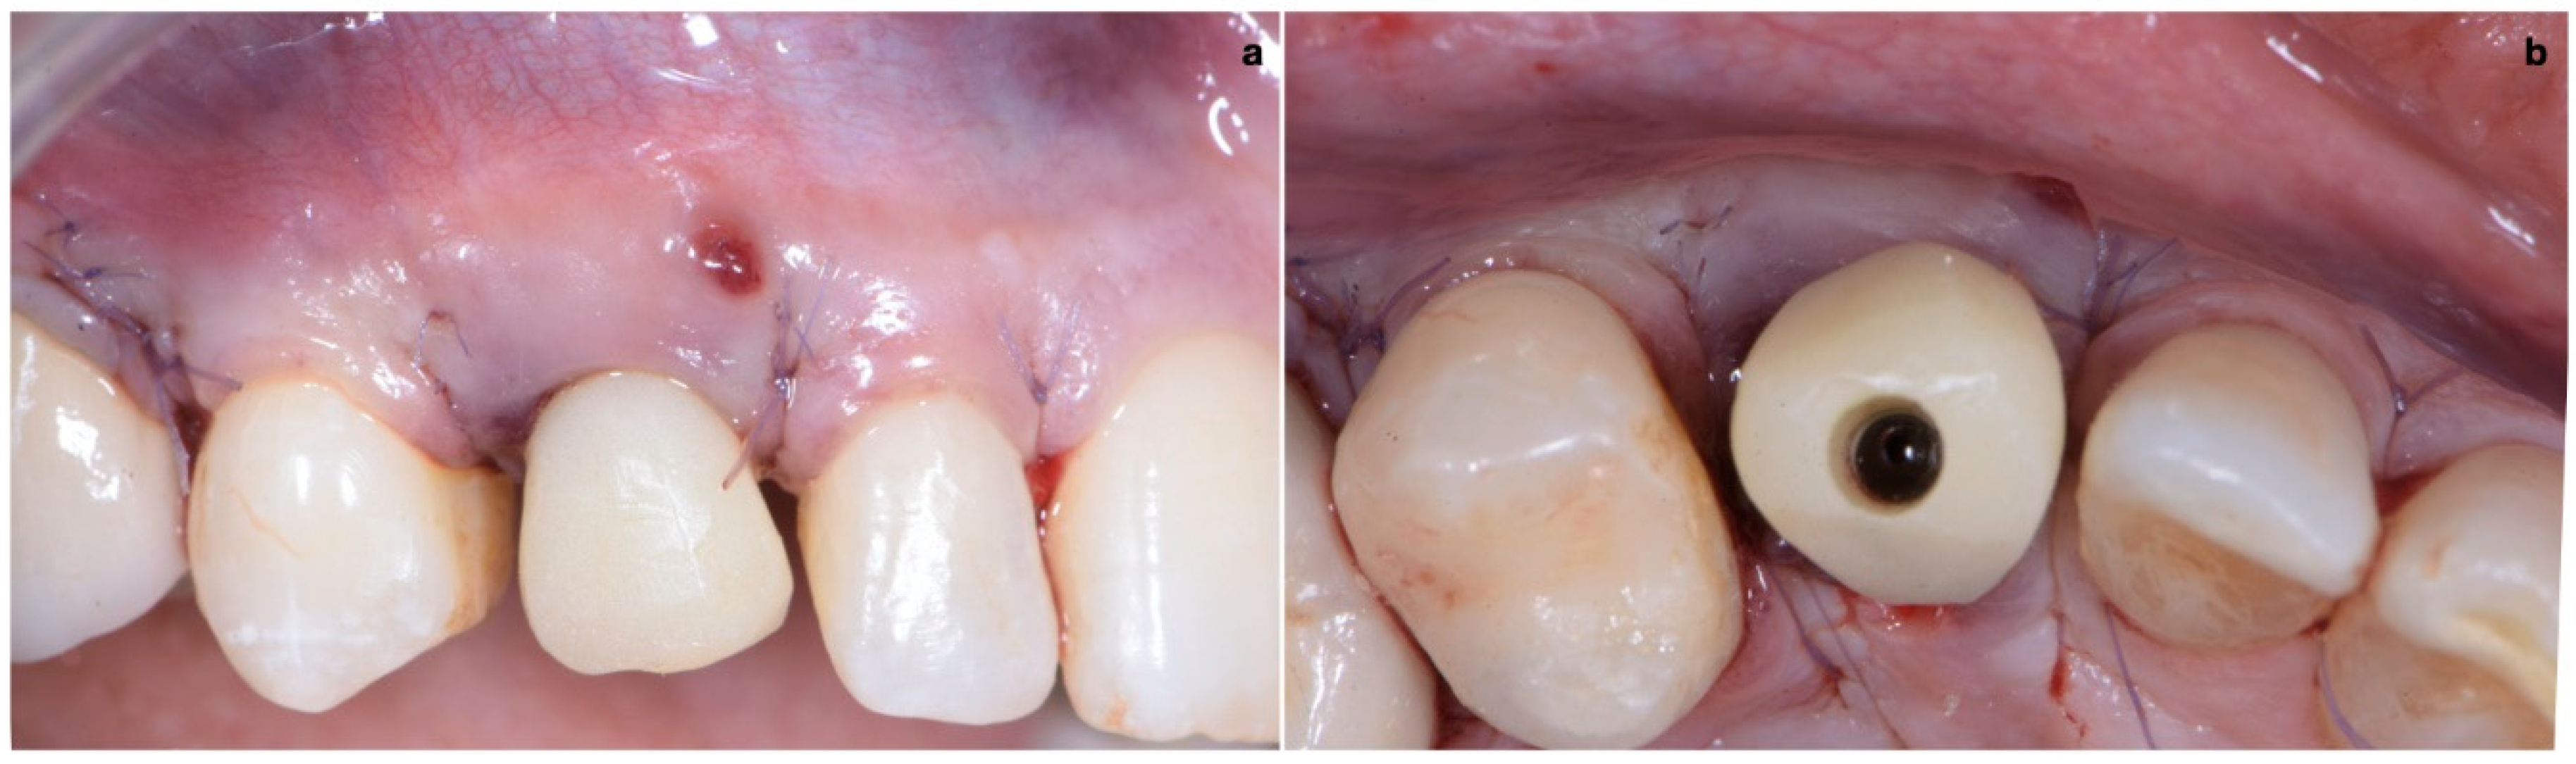

The closure of the surgical papilla over the anatomical papilla was performed with simple interrupted sutures (7/0 thread; 8 mm needle). First, we sutured the weakest papilla (in this case, the mesial one) before placing the provisional crown (Figure 10); this simplified suturing and made it possible to obtain an ideal adaptation of the surgical papilla on top of the smaller anatomical papilla. After screwing the provisional, it was time to suture the second surgical papilla (the distal one) onto the larger anatomical papilla with another simple interrupted suture (Figure 11a,b).

Figure 4. (a,b) Lateral-approach coronally advanced envelope flap, with oblique submarginal interproximal incisions directed towards the flap’s center of rotation (the tooth to be extracted).